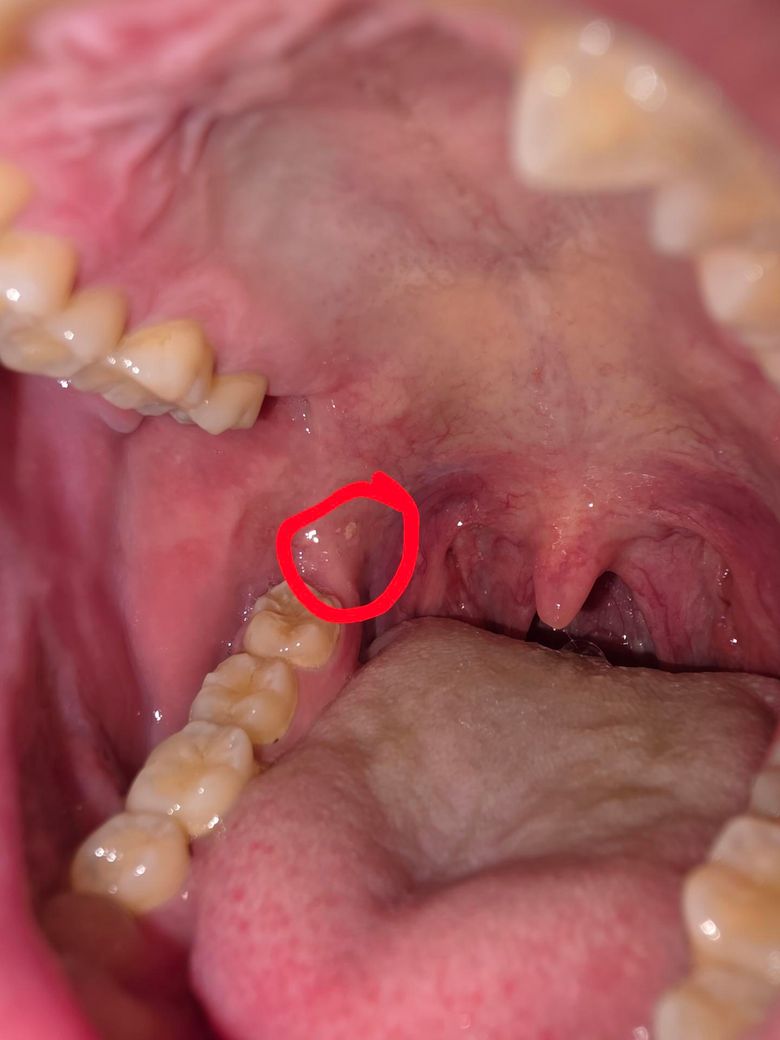

입속 하얀색 반점같은게 보이는데 뭘까요??

요 몇일간 코와 목 사이가 건조하고

수분을 섭취해도 자꾸 마르고 따가워서

편도선염인가 싶어 입안을보니

어금니 뒤쪽에 조그만 흰색반점같은게

눈에 띄어서 이게 뭔가 궁금해서 글적어봅니다.

이물감이 느껴지거나 아프진않습니다.

• 1번 째 사진

• 주어진 정보들을 토대로 판단을 하였을 때에는 궤양성 병변이 보이는 것으로 보아 구내염 소견일 가능성이 가장 높아 보입니다. 컨디션 조절을 하고 충분한 휴식 및 숙면을 취해주며 관리하면 스스로 호전될 가능성이 높아 보이는 소견이긴 합니다. 그렇지만 시간이 경과하도록 차도가 없거나 점점 심해지는 양상이라면 이비인후과적으로 한 번 진료, 진단 및 치료를 받아보는 것이 도움이 될 수도 있겠습니다.

먼저 구내염의 가능성에 대해 충분한 휴식과 균형 잡힌 영양의 섭취를 하고 구내염 연고를 발라보기 바랍니다.

만일 지속된다면 이비인후과 진찰을 받을 것을 권합니다.